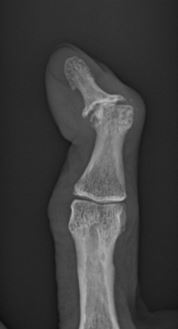

Psoriatic arthritis is experienced by less than a third of people with psoriasis, a skin condition caused by an overactive immune system. This type of arthritis often affects a person's fingers and toes.Lupus